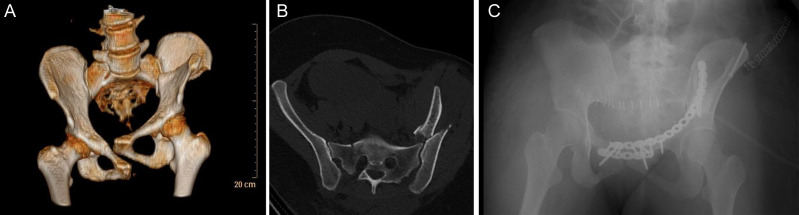

本研究旨在回顾地震创伤导致的骨盆损伤的特征和分类,确定治疗方案和结果,并介绍我们这个创伤中心的经验。本研究分析了地震后因骨盆环损伤接受手术治疗的 60 名患者(23 名男性,37 名女性)。研究记录了年龄、性别、手术和骨折细节等人口统计学数据。化验结果和用血量也包括在分析中。骨折根据 Young-Burgess 分类法进行分类。使用 SPSS 软件分析了手术治疗方法、受伤侧、伴伤和治疗结果。左侧创伤是最常见的损伤机制,36 名患者(60%)发生了左侧骨盆骨折。78.3%的患者发现骨盆环骨折,21.7%的患者发现髋臼和骨盆环合并骨折。分别有 12 例(20%)和 18 例(30%)患者出现胸部创伤和骨盆外骨折。20%的患者在骨盆手术前接受了紧急腹部手术。早期有 7 名患者(11.6%)出现并发症。患者的平均用血量为 2.91 U(最少:0,最多:13 U,平均值:2.66)。这项研究向我们表明,侧压伤更为常见,低血红蛋白水平、高炎症指标、既往腹部手术、伴有骨折和肺损伤是地震相关骨盆损伤患者的主要特征。该研究还表明,要优化材料和植入物的使用,需要不同技术的经验,并表明在治疗这些损伤时非常需要输血。四级,治疗研究。

The aim of this study was to review the characteristics and classifications of pelvic injuries due to earthquake trauma, to determine the treatment options and outcomes, and to present the experiences of our single trauma center. Sixty patients (23 male, 37 female) who underwent surgical treatment for pelvic ring injuries after the earthquake were analyzed in this study. Demographic data, such as age and gender, operations, and fracture details were recorded. Laboratory results and the amount of blood used were included in the analysis. Fractures were classified according to the Young-Burgess classification. Surgical treatment methods, side of injury, accompanying injuries, and treatment results were analyzed using SPSS software. Left-sided trauma was the most common mechanism of injury, with 36 patients (60%) sustaining left-sided pelvic fractures. Pelvic ring fractures were detected in 78.3% of patients, and combined acetabulum and pelvic ring fractures were identified in 21.7% of patients. Thoracic trauma and extra-pelvic fractures were seen in 12 (20%) and 18 (30%) patients, respectively. Twenty percent of patients underwent emergency abdominal surgery prior to pelvic surgery. Complications were observed in 7 patients (11.6%) in the early period. The average amount of blood used for patients was 2.91 U (min: 0, max: 13 U, SD: 2.66). This study has shown us that lateral compression injuries are more common, and that low hemoglobin levels, high inflammation parameters, previous abdominal surgery, accompanying fractures, and lung injury are the main characteristics of patients with earthquake-related pelvic injuries. It also demonstrates that for the optimal use of materials and implants, experience in different techniques is required, and shows the significant need for blood transfusions in the treatment of these injuries. Level IV, Therapeutic study.